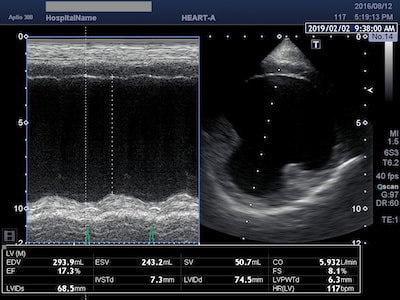

拡張型心筋症(DCM)

大型犬に多くみられる拡張型心筋症(DCM)は、心筋が薄くなることにより心臓の収縮力が低下し、その結果心臓が拡張してしまいます。進行すると心拍出量の低下を招き心不全に陥る怖い疾患です。残念ながら現在のところDCMを治す有効な治療薬は存在しませんが、心臓の収縮力を助けるお薬で従来よりも長生きできるわんちゃんが増えてきました。

拘束型心筋症(RCM)

肥大型心筋症(HCM)と並んで、猫によくみられる心筋症の一つが拘束型心筋症(RCM)です。HCMと違って心筋の肥大は認められませんが、心内膜の線維化や、心室内に過剰な線維性構造物(過剰調節帯)が認められ、心臓の動きが悪くなる(拘束される)のが特徴です。

RCMに伴う胸水と左房内血栓

RCMでは心室の動きが拘束されることにより拡張機能が妨げられ、僧帽弁逆流や三尖弁逆流が生じた結果、左房拡大や右房拡大が顕著に認められます。拡張した心房内では血流の鬱滞や乱流が生じるため、肺水腫や胸水の貯留、血栓が生じやすくなります。治療には血管拡張薬や利尿剤、血栓予防薬を用います。